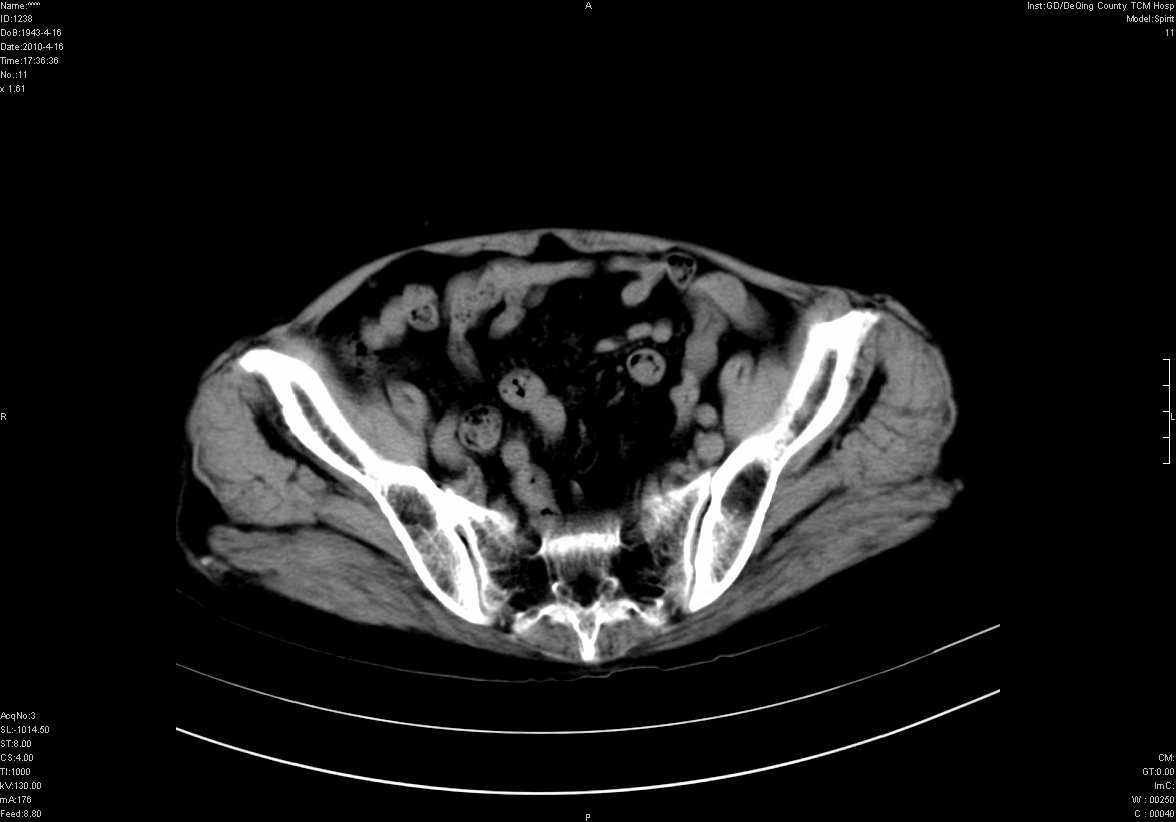

标题: CT25796:女,60岁,腹痛5天,请会诊??? [打印本页]

标题: CT25796:女,60岁,腹痛5天,请会诊???

考虑卵巢畸胎瘤。

支持右侧盆腔畸胎瘤。

畸胎瘤

右侧附件畸胎瘤

考虑右侧卵巢畸胎瘤。

考虑右侧卵巢畸胎瘤

右侧卵巢畸胎瘤可能。